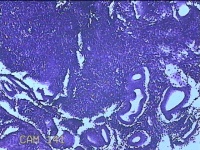

宫腔刮出物

性别

女

年龄

54岁

临床诊断

宫内节育器

一般病史

下腹隐痛一年余。

标本名称

大体所见

灰白暗红色不规则碎组织1x0.8x0.3cm一堆。